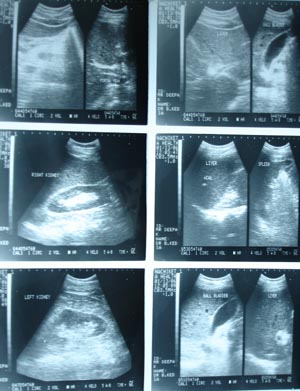

USG.Normal

The routine USG for medicosurgical purpose is done in a systemic way of performance. Unless and until, specified about target organ the sonographer usually include all the structures of the abdomen. Start with liver in all planes, kidney in short & long axis, spleen, pancreas, vessels, particularly IVC & Aorta with any visible LN in any group. Bladder has to be full for evaluation of genitourinary tract.